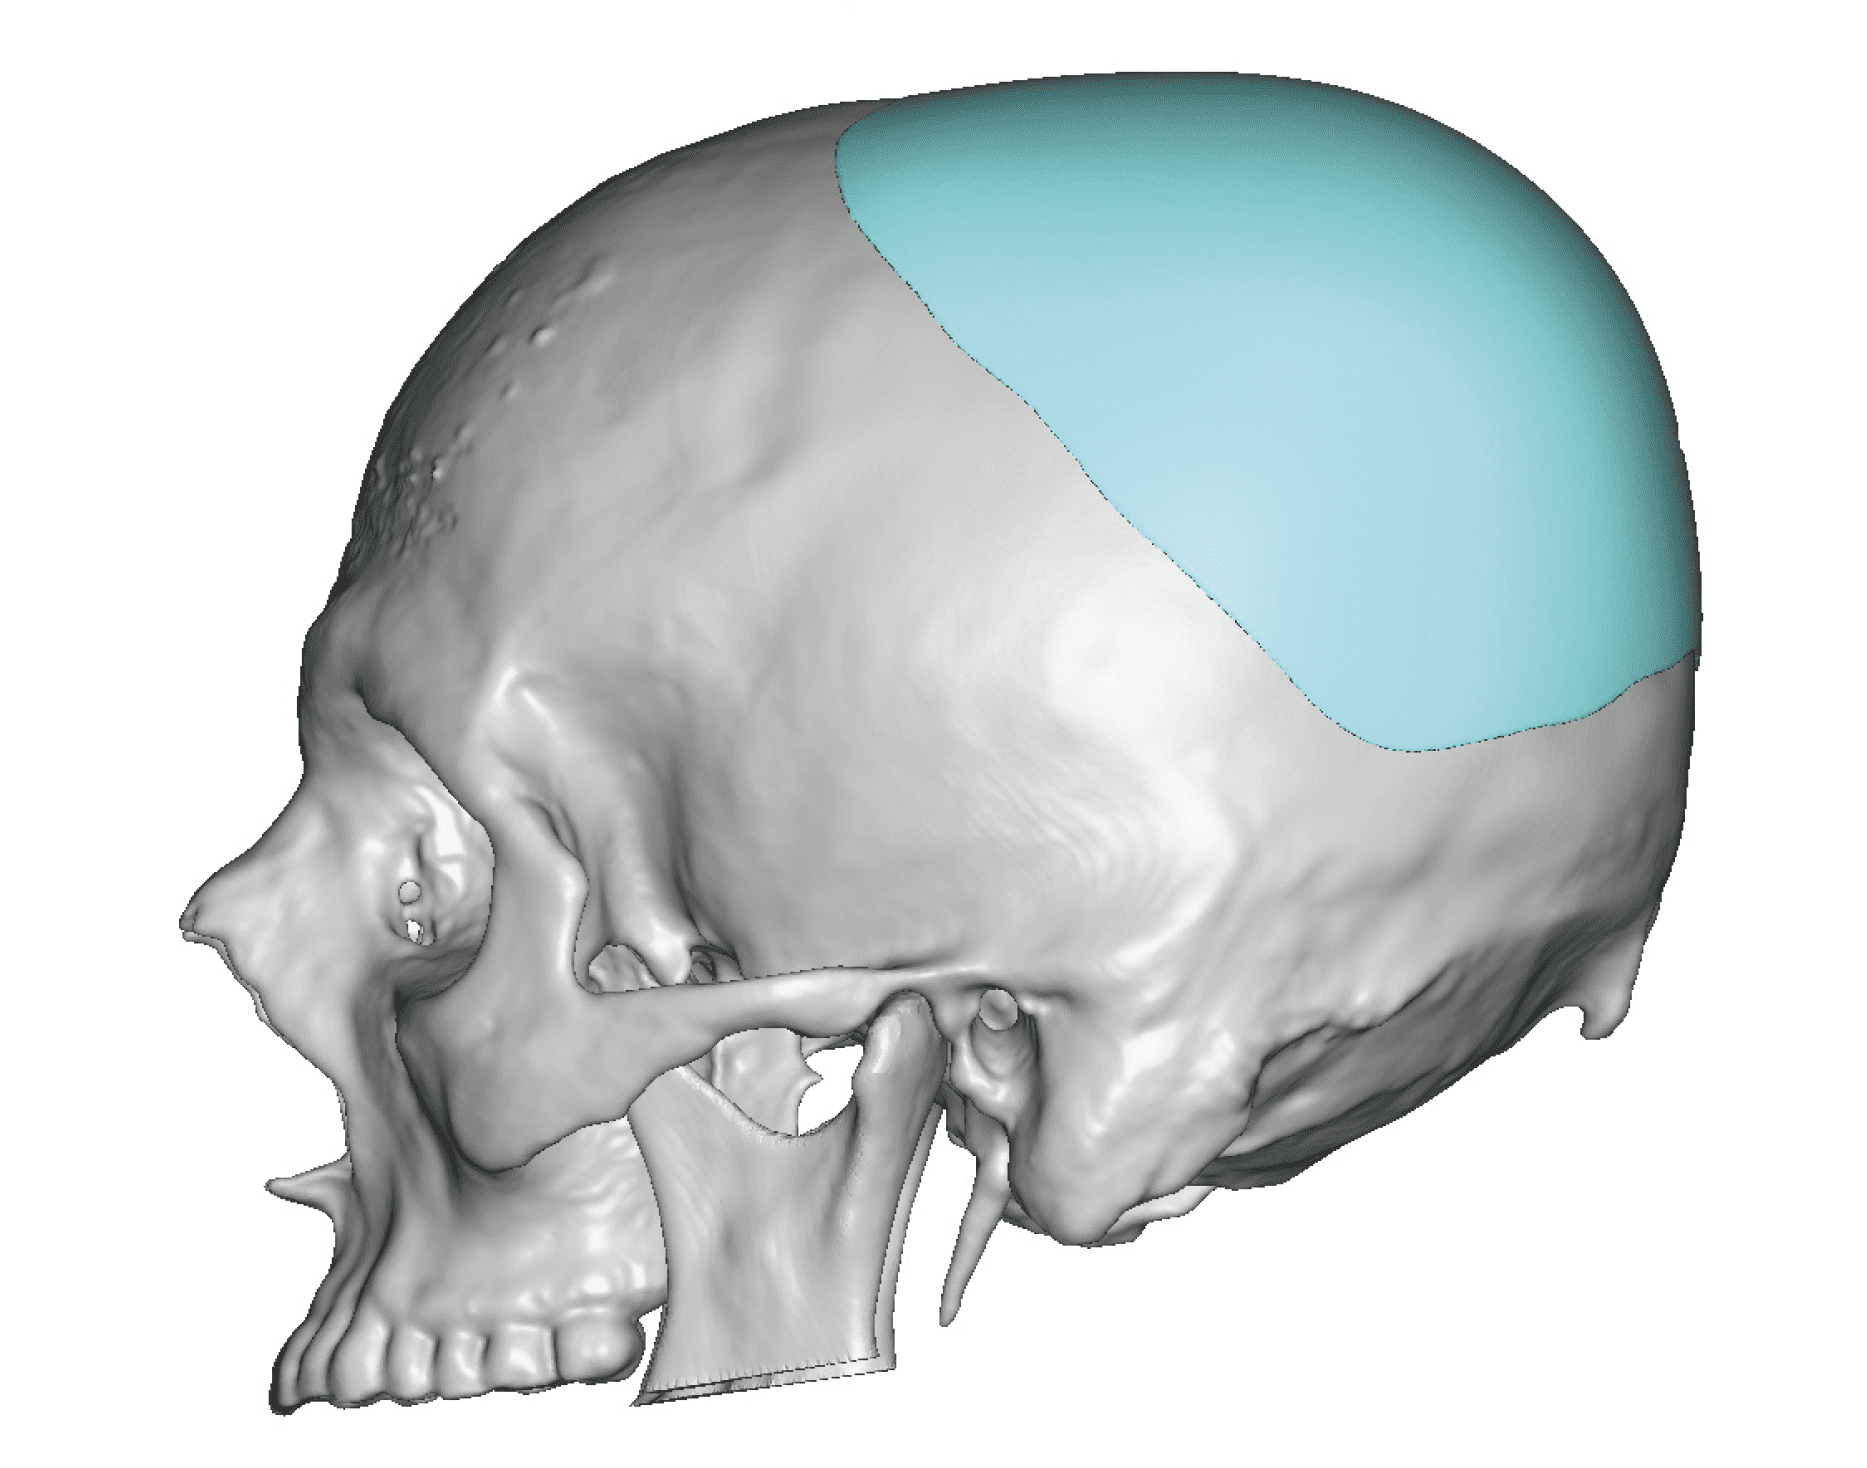

Severe narrowing skull deformity from prior sagittal craniosynostosis repair as an adult.

Complete replacement of entire skull by a custom implant with temporal fat injections.